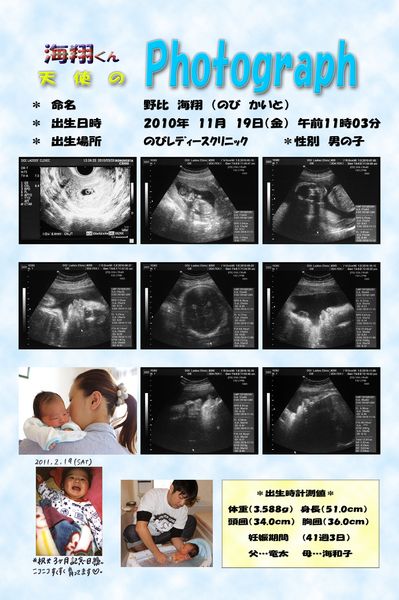

[ お買い物 ] 写真の事なら 野比写真工房